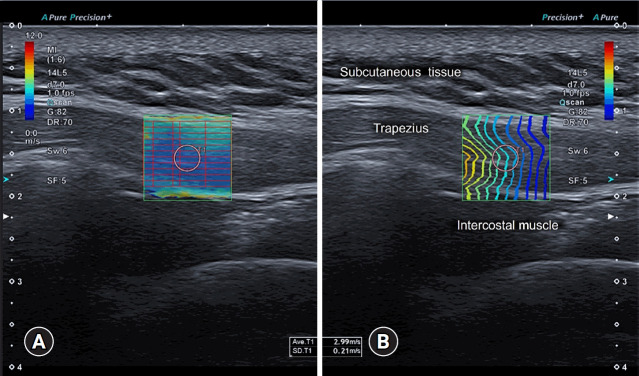

Myofascial pain syndrome (MPS) is a common musculoskeletal disorder characterized by muscle pain, tenderness, and trigger points. Ultrasonography has emerged as a key tool for diagnosing and treating MPS owing to its ability to provide precise, minimally invasive guidance. This review discusses the use of ultrasonography in various approaches to evaluate and manage MPS. Studies have shown that shear-wave sonoelastography can effectively assess muscle elasticity and offer insights into trapezius stiffness in patients with MPS. Ultrasound-guided interfascial hydrodissection, especially with visual feedback, has demonstrated effectiveness in treating trapezius MPS. Similarly, ultrasound-guided rhomboid interfascial plane blocks and perimysium dissection for posterior shoulder MPS have significantly reduced pain and improved quality of life. The combination of extracorporeal shockwave therapy with ultrasound-guided lidocaine injections has been particularly successful in reducing pain and stiffness in trapezius MPS. Research regarding various guided injections, including dry needling, interfascial plane blocks, and fascial hydrodissection, emphasizes the importance of ultrasonography for accuracy and safety. Additionally, ultrasound-guided delivery of local anesthetics and steroids to the quadratus lumborum muscle has shown lasting pain relief over a 6-month period. Overall, these findings highlight the pivotal role of ultrasonography in the assessment and treatment of MPS.